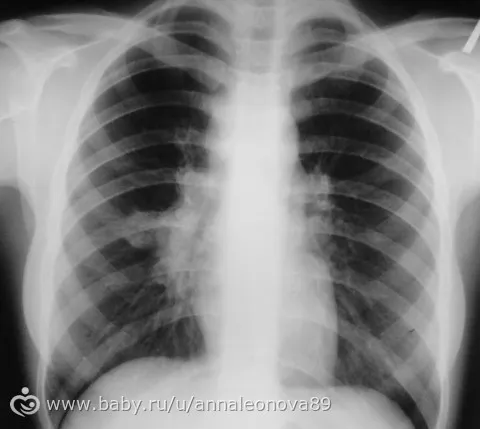

2. Рентгенография грудной клетки.